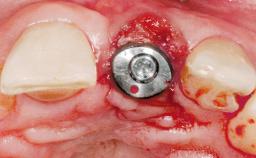

A 30-year-old female patient was referred to the office for the treatment of tooth 11. Her chief concern at the initial visit was to inquire, “Why is my tooth pink?” Upon clinical examination, it was determined that tooth 11 had a previous history of trauma and that the clinical crown had become noticeably pink in color as a result of internal resorption. This diagnosis was confirmed radiographically, indicating a large radiolucency involving the central and distal portions of the clinical crown. It was determined that restoration of this tooth was not possible, and that extraction was indicated. The presence of a mid-line diastema, which the patient wanted to reproduce, directed the treatment plan for tooth replacement utilizing a dental implant.

Type of Implants One-Piece|Reduced-Diameter

Bone Augmentation Horizontal|Simultaneous

Augmentation Materials Autogenous chips|Membrane

Abutment Type Standard

Placement Protocol Immediate implant placement

Socket Integrity Sufficient, with intact bone walls

Bone Volume Sufficient, with intact walls